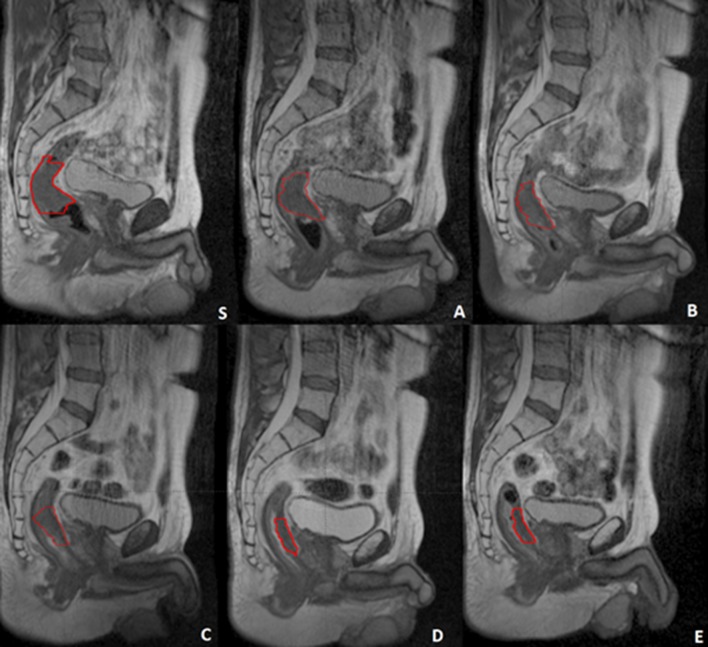

Figure 1 shows the imaging protocol applied in a case where a clinical complete response was achieved. The red contour indicates the GTV delineation.

Fig. 1.

The complete image set of a patient from first simulation acquisition (t0 Gy) (S) to last fraction (t55 Gy) (a–e). The GTV is represented by the red contour